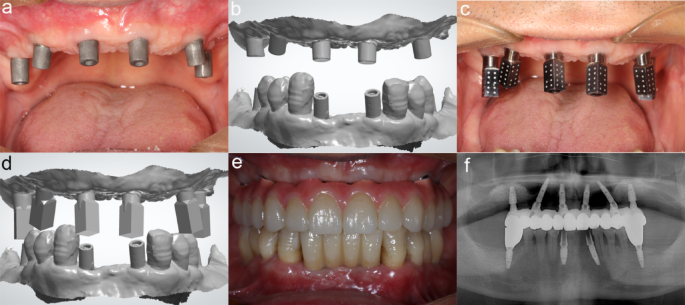

During the second stage of surgery, the screw-retained abutments were replaced after the implants in zone 3 achieved osseointegration. The immediate short arch restoration was removed, and scan bodies were connected to the implants to capture the soft tissue contours using TRIOS 4 (3Shape A/S, Denmark) (Fig. 5a, b). The scan bodies were then replaced and scanned with ICam4D (Imetric4D Imaging Sàrl, Switzerland) to determine the three-dimensional positions of the implants (Fig. 5c, d). A digital model capturing the occlusal relationship was created by intraoral scanning the immediate prosthesis with the oral scanner. Digital models of the soft tissue contours, implant positions, and occlusal relationships were aligned, leading to the design and fabrication of the final prostheses, which were completed and placed (Fig. 5e). Panoramic imaging was again performed to verify the proper positioning of the prosthesis (Fig. 5f). Finally, a postoperative CBCT was conducted to evaluate the bone levels surrounding the implants.

Final restoration. (a, b) Intraoral scanning for soft tissue contour. (c, d) Intraoral scanning for the position of implants. (e) Picture of final restoration in mouth. (f) Panoramic imaging of final restoration.